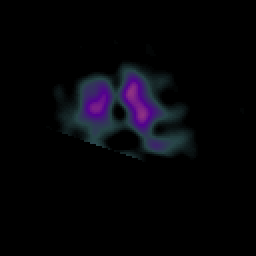

Alzheimer's disease: Perfusion SPECT -- Slice #43

[Home][Help][Clinical][Tour 1][Tour 2] Slice 43